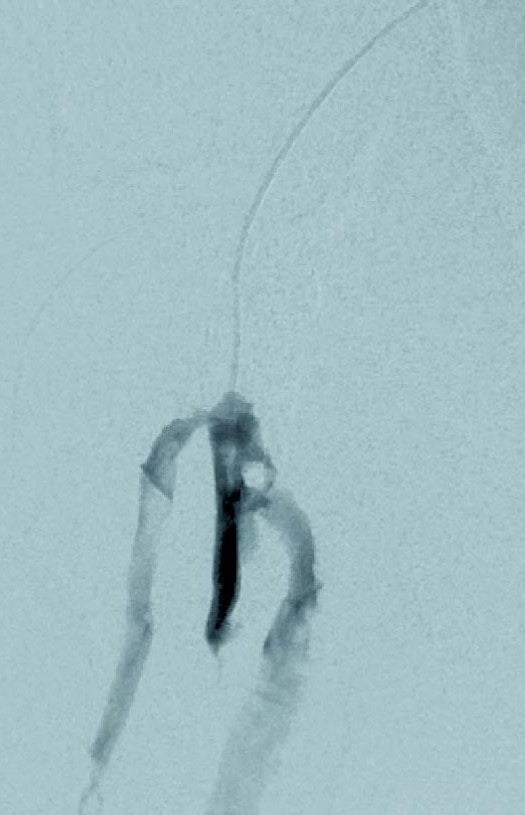

右CFAの狭窄が疑われたため、対側の左CFA逆行性アプローチとした。6 Frガイティングカテーテル45 cmを山越えし、右EIAに留置した。右CFAの造影で石灰化による有意狭窄を認めたため、6 mm × 20 mmのcutting balloonで十分に拡張した。続いて、右SFAは10 mmほどの入口部を認めたため、慎重にCTO proximal capにアプローチした。同部位より5.5 Frインナーガイディングカテーテル、0.014 inchガイドワイヤー対応のIVUS、0.014 inchのCTO用ワイヤーの組み合わせで、入口部のtrue lumenを確保しCTOに侵入した。IVUS knuckle法でtrue lumenであることを確認しながらガイドワイヤーを進めた。

入口部からアテローム性血栓内を130 mmほど進んだところで高度石灰化部位に到達した。同部位は4 Fr造影カテーテル、0.035 inchのガイドワイヤー(先端Jカーブ)の組み合わせで石灰化を滑らせるように抜けた。最後のdistal capは0.014 inchのCTO 用ワイヤーでdrillingしてtrue lumenへ抜けた。

病変長が290 mmと長く、石灰化が高度であったこと、中枢のhealthy landingが10 mm長かったことからバイアバーン® ステントグラフトを選択した。3 mm × 300 mmのバルーンで前拡張するもバイアバーン® ステントグラフトは通過しなかったため、5 mm × 300 mmバルーンで拡張し、さらに0.018 inchのスティッフタイプのガイドワイヤーに入れ替えバイアバーン® ステントグラフトをdeliveryした。末梢にバイアバーン® ステントグラフト5 mm × 150 mmおよび、中枢側に6 mm × 250 mmを留置し病変をフルカバーした。5 mm × 300 mmのバルーンで20気圧まで圧を上げてしっかり後拡張を行った。